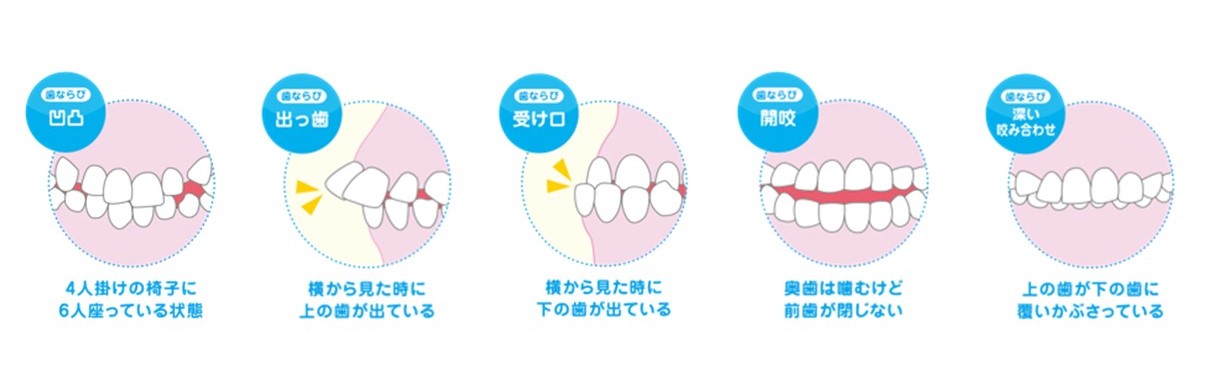

子どもの歯並びで気になる症状ございませんか?

上記の症状以外にも下記のような症状もございませんか?

- 前歯が出ている、もしくは引っ込んでいる

- 歯並びがガタガタしている

- 口がポカンと開いていることが多い

- 食事のときにうまく噛めていない

- 発音がはっきりしない、話しづらそう

- 指しゃぶりや舌を前に出す癖がある

- 顎が小さい、またはしゃくれているように見える

- 歯医者さんに「永久歯が生えるスペースが足りない」と言われた